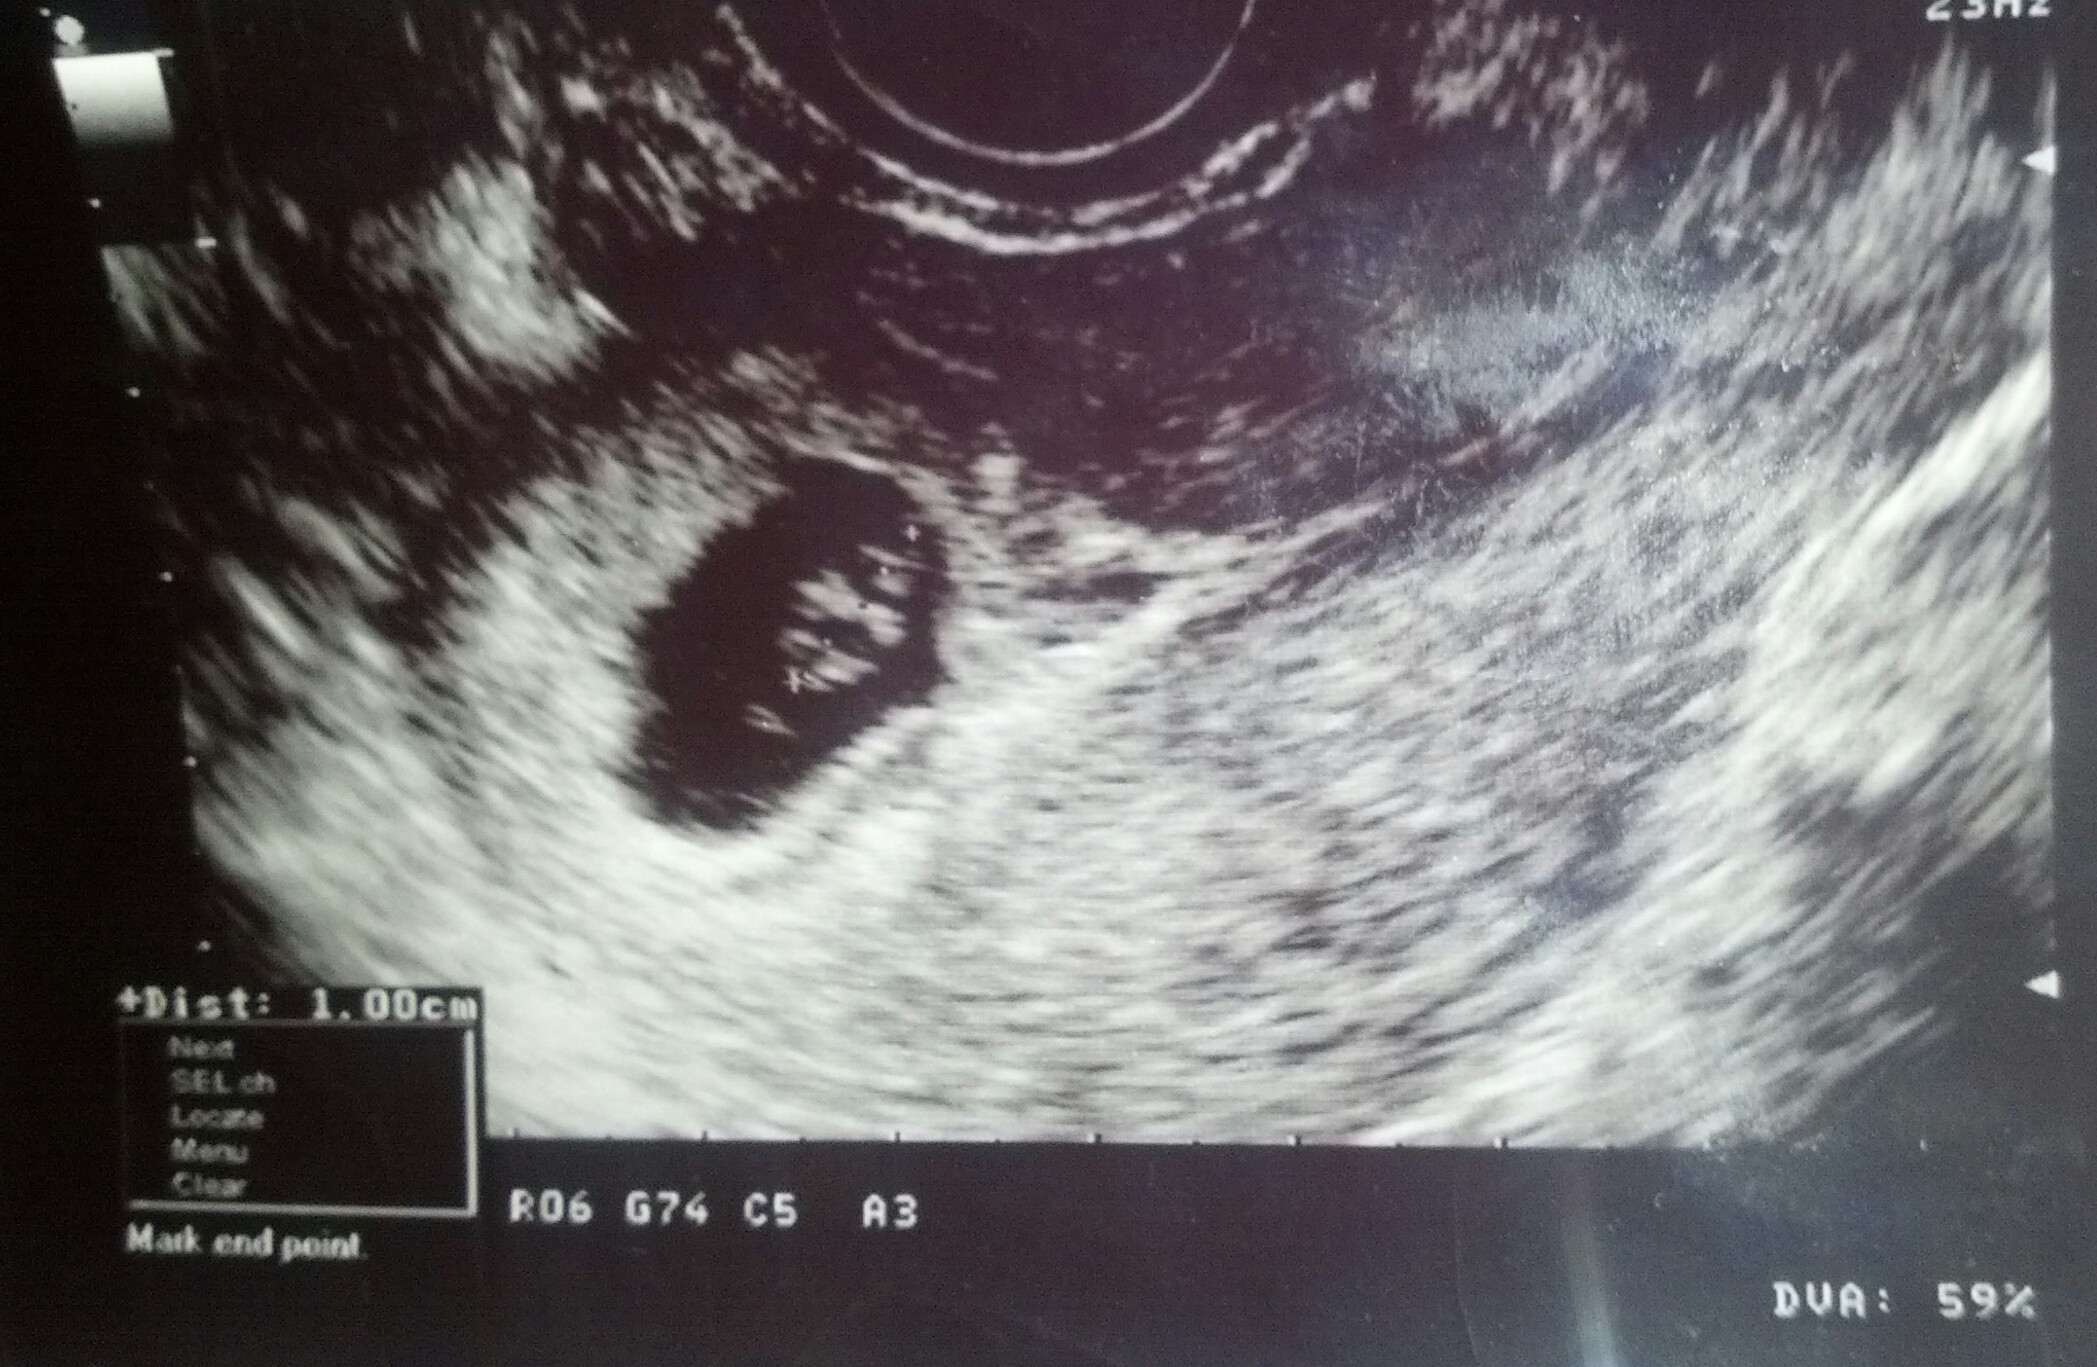

Hi ladies, had a scan today at 6 weeks

Scan: transvaginal

Plane: sagital

Orientation: my right side is on the right and my left side is on the left of the picture.

Any one who is comfortable to help explain your guess.